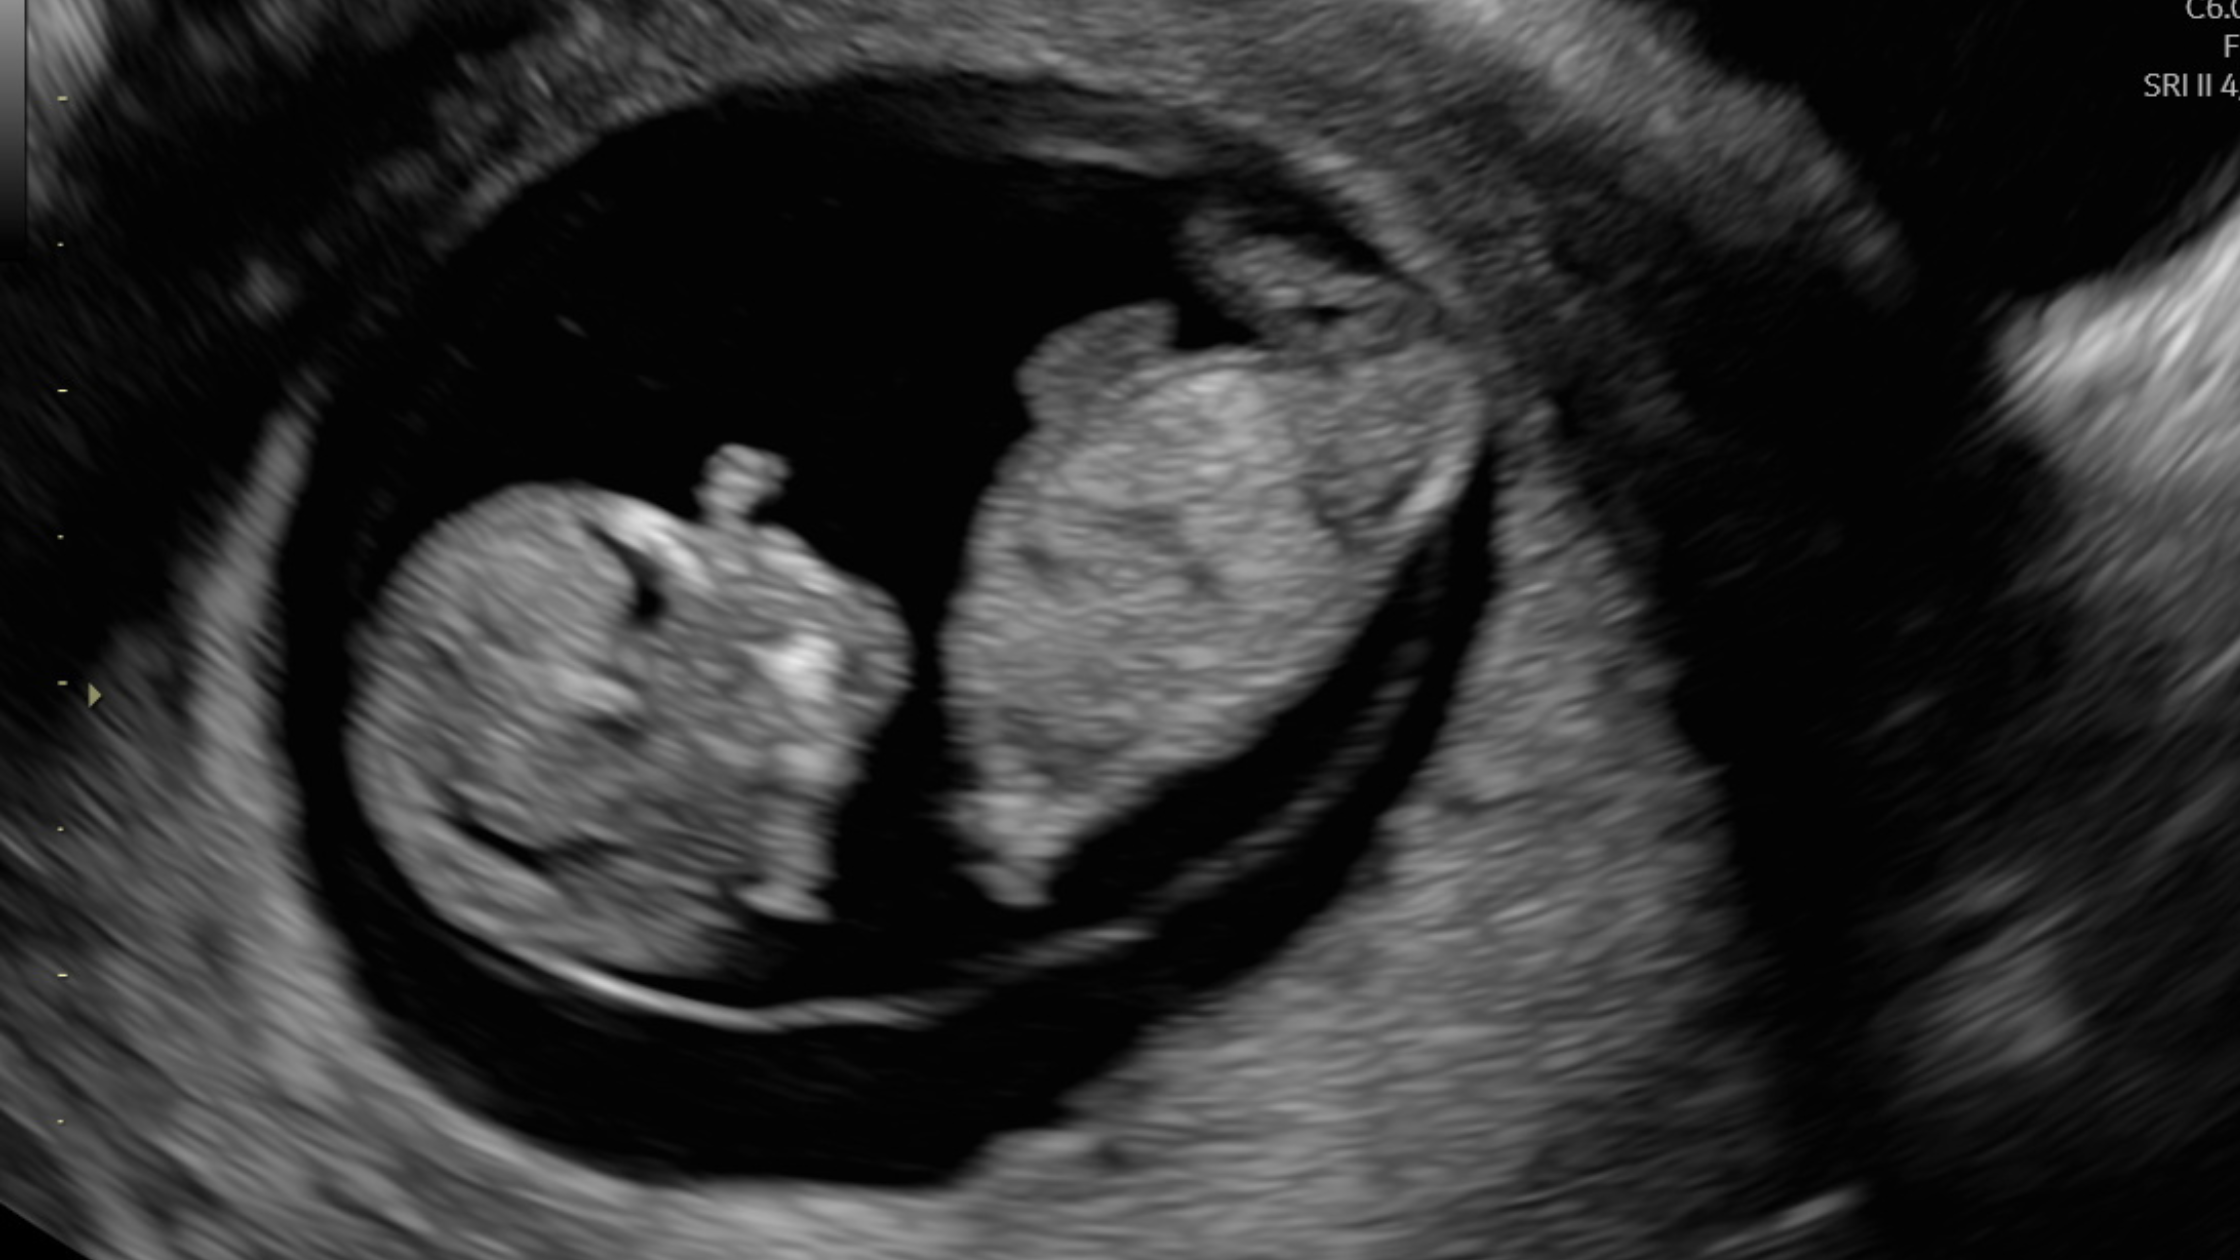

Take a Peek at Your Baby: The Benefits of 4D Scans at Our Clinic

There’s nothing quite like the moment when you see your baby on screen – and thanks to 4D ultrasound scanning, that moment is more magical